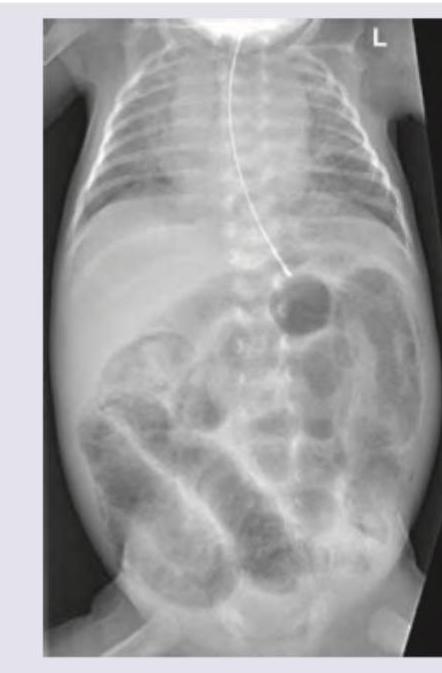

Identify the condition on the basis of infantogram shown in the image:

Explanation: ***Congenital diaphragmatic hernia*** - The infantogram shows loops of **bowel within the thoracic cavity**, displacing the heart and mediastinum. - This classic appearance, with visible **gas-filled loops** in the chest, is characteristic of a congenital diaphragmatic hernia, typically on the left side (Bochdalek hernia). *Cystic adenomatoid malformation* - This condition involves an abnormal growth of lung tissue forming **cysts**; these cysts typically appear as discrete radiolucencies or a solid mass within the lung. - Unlike in the image, it does not typically show distinct **bowel loops in the chest cavity**. *Pneumomediastinum* - This condition is characterized by air in the **mediastinum**, which would appear as lucency outlining the mediastinal structures, such as the heart and great vessels. - It does not involve the presence of **abdominal contents** within the chest cavity. *Congenital lobar emphysema* - This condition presents with **hyperinflation of a single lobe** (usually left upper lobe) causing mass effect and mediastinal shift. - It appears as a hyperlucent, overexpanded lobe, but does not show **bowel gas pattern** or abdominal contents in the thorax.